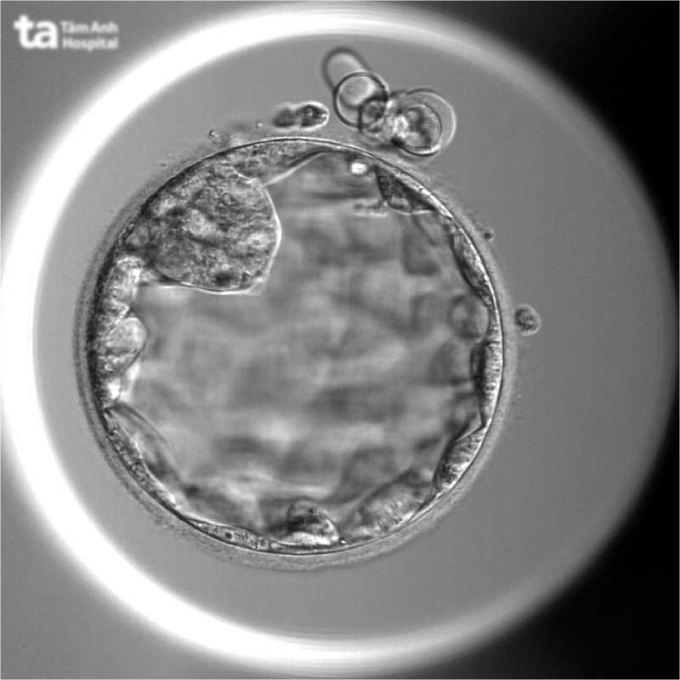

Bác sĩ Thủy kích thích buồng trứng cho bệnh nhân, thu 19 trứng, hầu hết có hình thái móp méo, bào tương rỗ, không phát triển đến giai đoạn trưởng thành. Chuyên viên phôi học nỗ lực lọc rửa, tiếp tục nuôi cấy toàn bộ trứng trong môi trường tối ưu và chọn lọc được 14 trứng đủ điều kiện để thụ tinh cùng tinh trùng của người chồng. Kết quả thu được 3 phôi ngày 3, tiếp tục nuôi lên giai đoạn ngày 5 thì hai phôi ngừng phát triển, còn phôi duy nhất vượt qua sàng lọc tự nhiên khắc nghiệt. Phần mềm trí tuệ nhân tạo (AI) chấm điểm chất lượng phôi loại 3, mức độ trung bình.

Hình ảnh phôi ngày 5 được nuôi cấy tại IVF Tâm Anh TP HCM. Ảnh: Thu Thảo